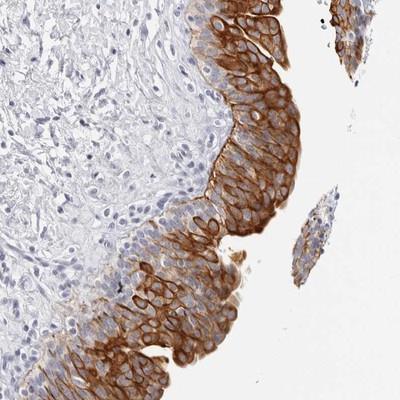

- Main image

- Experimental details

- Immunohistochemistry-Paraffin: RPH3AL Antibody [NBP1-80991] - Staining of human urinary bladder shows strong cytoplasmic positivity in urothelial cells.